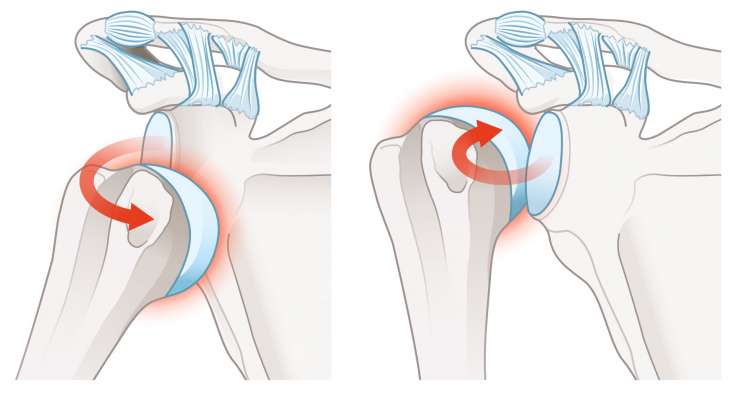

Вывих плеча

Вывих плеча, то есть вывих головки плечевой кости из суставной впадины, профессор, доктор медицины Франк Мартечшлегер лечит консервативно или артроскопически, в зависимости от степени травмы, с целью восстановления стабильности плеча надолго.